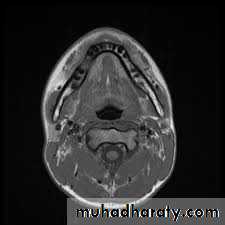

Magnetic resonance imaging (MRI) : is generally considered more valuable in the evaluation of soft tissue lesions of the maxillofacial region. However, MRI can assist in the early diagnosis of osteomyelitis by loss of the marrow signal before cortical erosion or sequestrum of the bone appears. Thus, MRI may benefit in identifying the earlier stages of osteomyelitis.

16